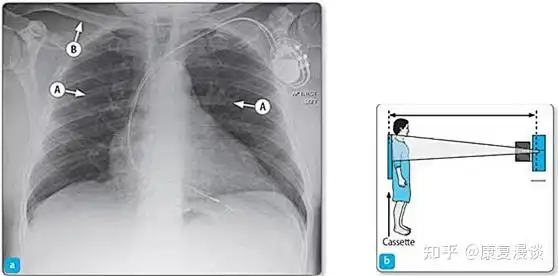

x线从患者背后穿透,患者前胸紧贴探测平板,双手背于髂骨上,肩部下垂